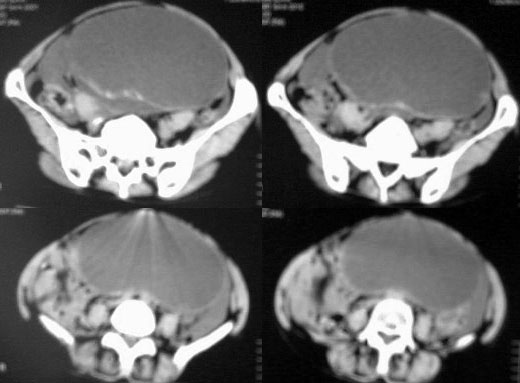

患者女性,45岁,因下腹疼痛,包块就诊,月经不太规则,其他未能提供有价值病史,请讨论

对不起各位,第一次试传,经验不足,补充一下资料,患者女性,45岁,因下腹疼痛,包块就诊,月经不太规则,其他未能提供有价值病史

1.卵巢囊性畸胎瘤,2. 卵巢囊腺癌,道格拉斯腔积液。

ct图像有点不连续,且大部画面模糊,有增强吗?就此而论我看向源于卵巢的,首先考虑囊腺ca或瘤.

此患者手术病理结果已出:卵巢囊腺瘤。